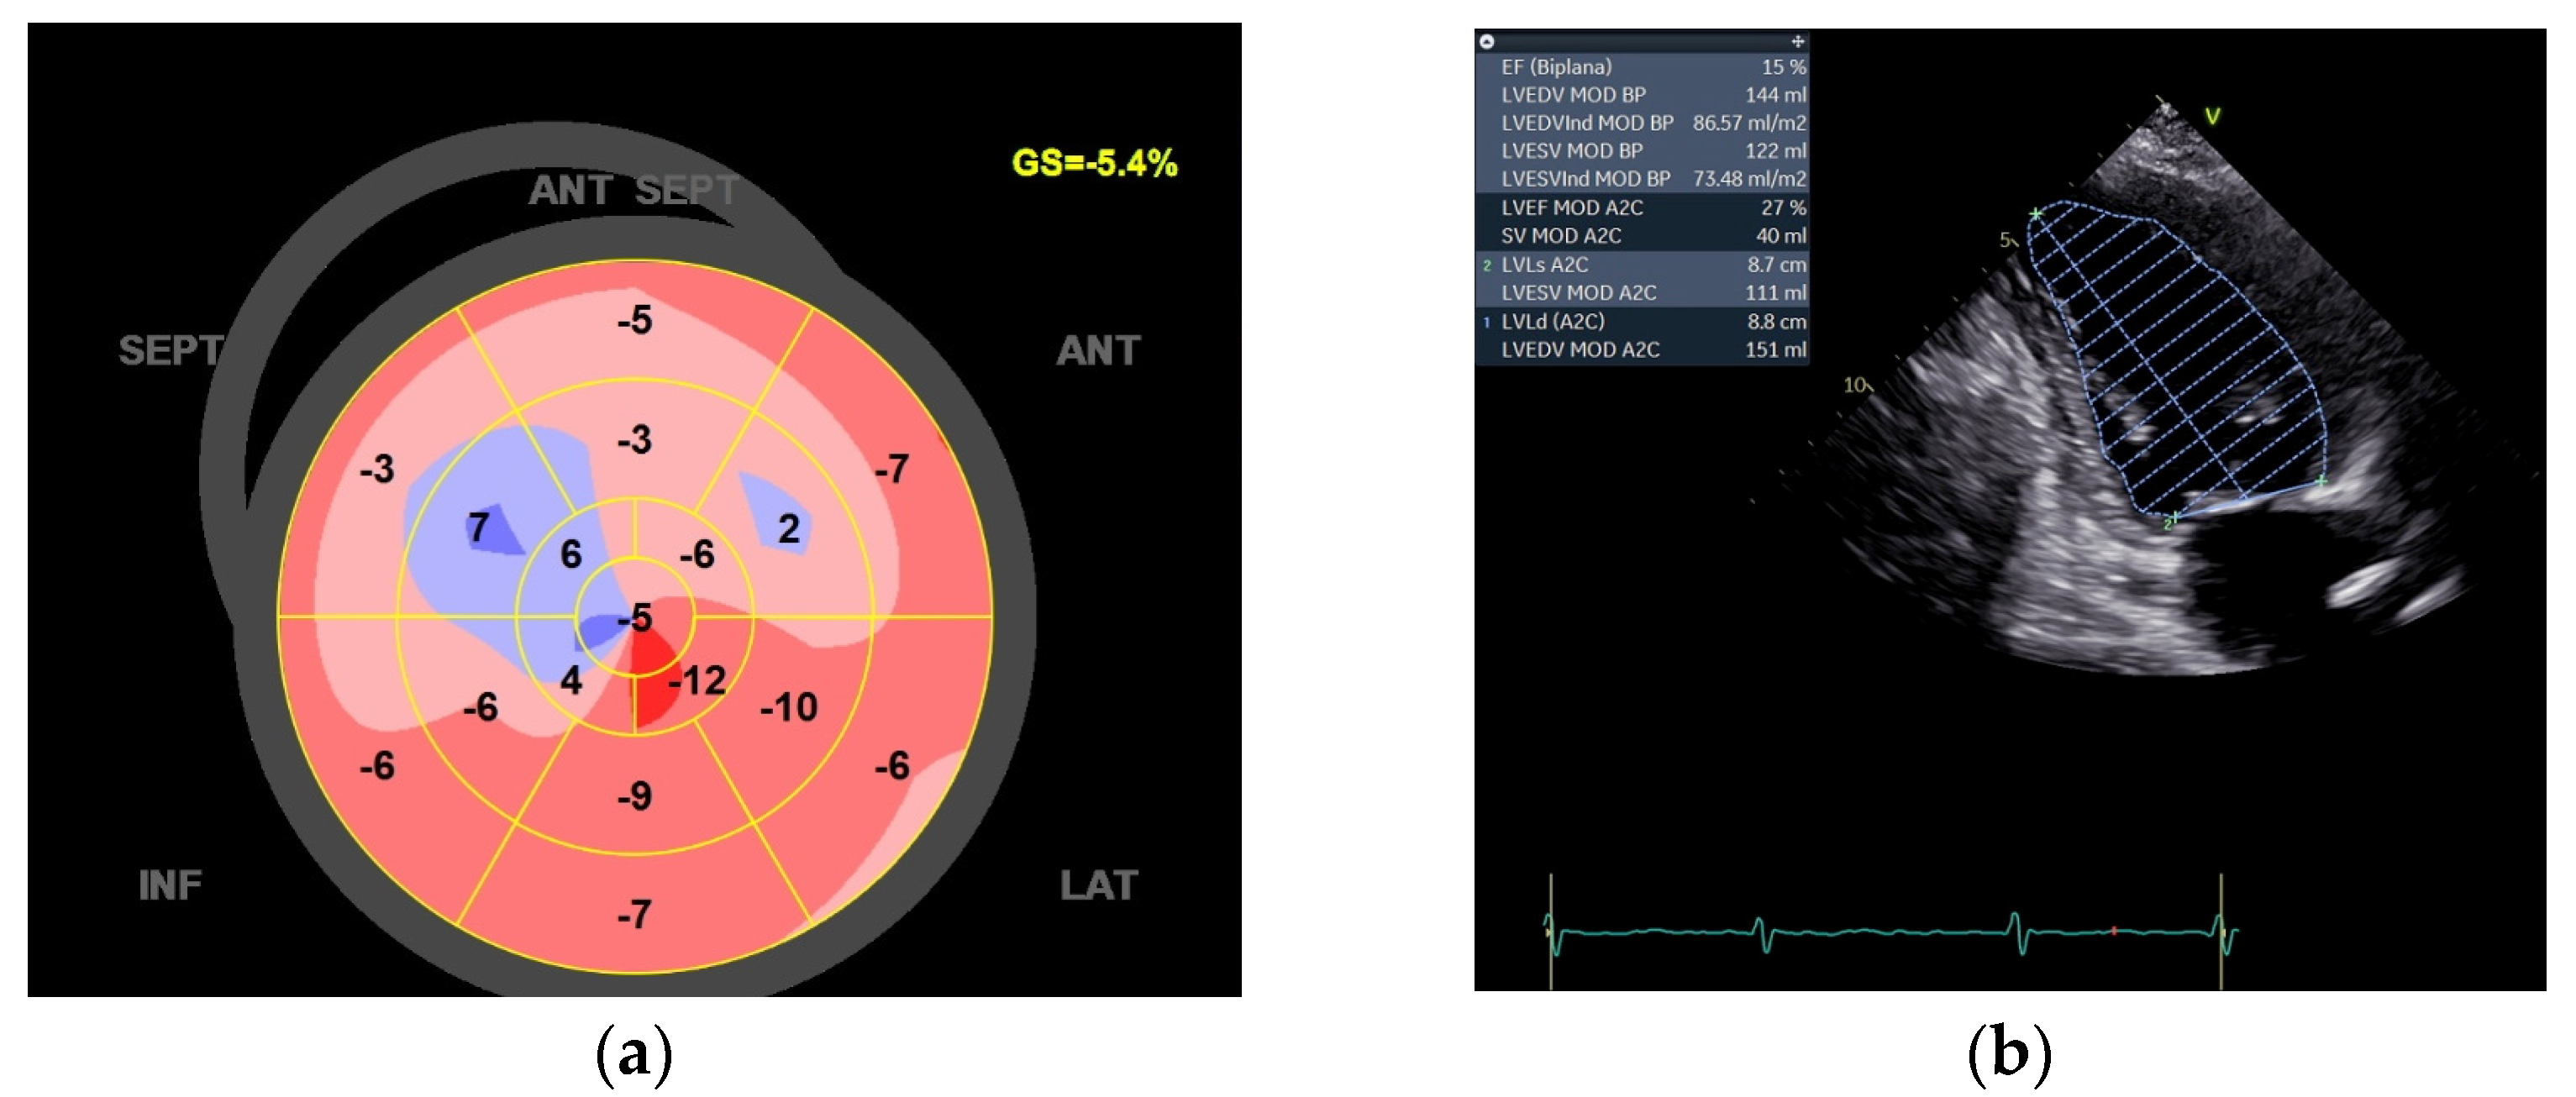

| 06/2022 | 09/2022 | 12/2022 | 03/2023 | 01/2024 | |

|---|---|---|---|---|---|

| EF 2ch (%) | 15 | 46 | 46 | 48 | 47 |

| LVEDV (mL) | 144 | 102 | 66 | 106 | 104 |

| LVESV (mL) | 122 | 56 | 36 | 49 | 51 |

| GLS (%) | −5.4 | −12.8 | −11.4 | −14.6 | −12.5 |

| LAa (cm2) | 22.6 | 26.1 | 21.3 | 19.5 | 11.8 |

| LAv (mL) | 64 | 90 | 67 | 56 | 23.4 |

| NT-proBNP | 2376 | 984 | 496 | 323 | 214 |

| KCCQ | 79.1 | 80.9 | 90 | 90 | 90 |

| MLWHFQ | 60 | 16 | 16 | 13 | 0 |